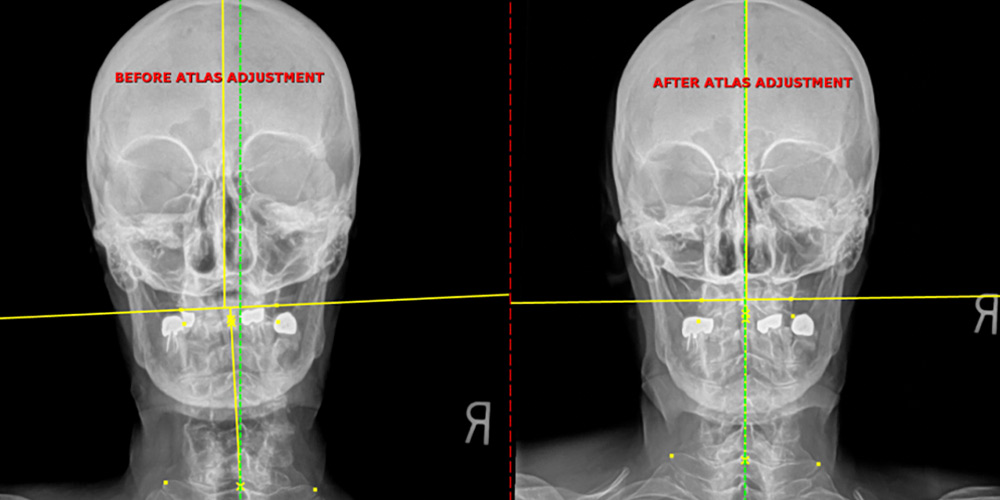

For those living with frequent, crippling headaches, migraines, or the debilitating spinning sensation of vertigo, the constant search for relief often leads to medication that only masks the pain. However, the root cause is frequently a mechanical issue: misalignments (subluxations) in the upper cervical spine (the top two bones of your neck). When these delicate vertebrae shift, often due to old trauma, whiplash, or chronic posture stress, they irritate the sensitive nerves (especially the trigeminal and suboccipital nerves) and affect blood flow to the brain, triggering migraines, tension headaches, and a form of dizziness known as Cervicogenic Vertigo.

Our approach uses Corrective Chiropractic Care and advanced neurological assessments to pinpoint the exact structural fault. We don't guess; we use precision adjustments to gently restore normal alignment to the upper neck, immediately relieving pressure on the nerves and stabilizing the neurological feedback loop that causes your symptoms.